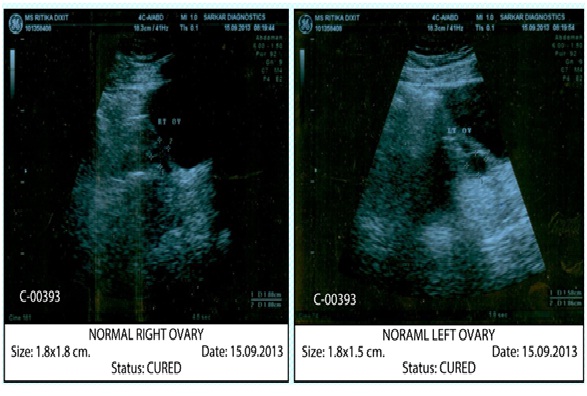

Image: After Treatment.

She started showing signs of improvement. Treatment was continued on the same lines. Her menses soon became regular. Hyper pigmentation also faded away slowly. Sonography reports showed normal results. Also her hormone levels became normal.